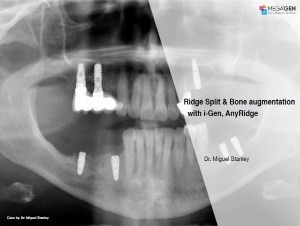

Ridge Split & Bone augmentation with i-Gen, AnyRidge

Dr. Miguel Stanley,Bone regeneration,Mandibular Posterior,Maxillary Posterior,#35,#36,#24,GBR,Ridge Split,Sinus Elevation,Immediate Placement,AnyRidge,Bio-Oss, i-Gen,SmarThor,BonEx Kit,Clinical case

English

2019-10-01

PDF

521.75 Kb

Clinical cases

232